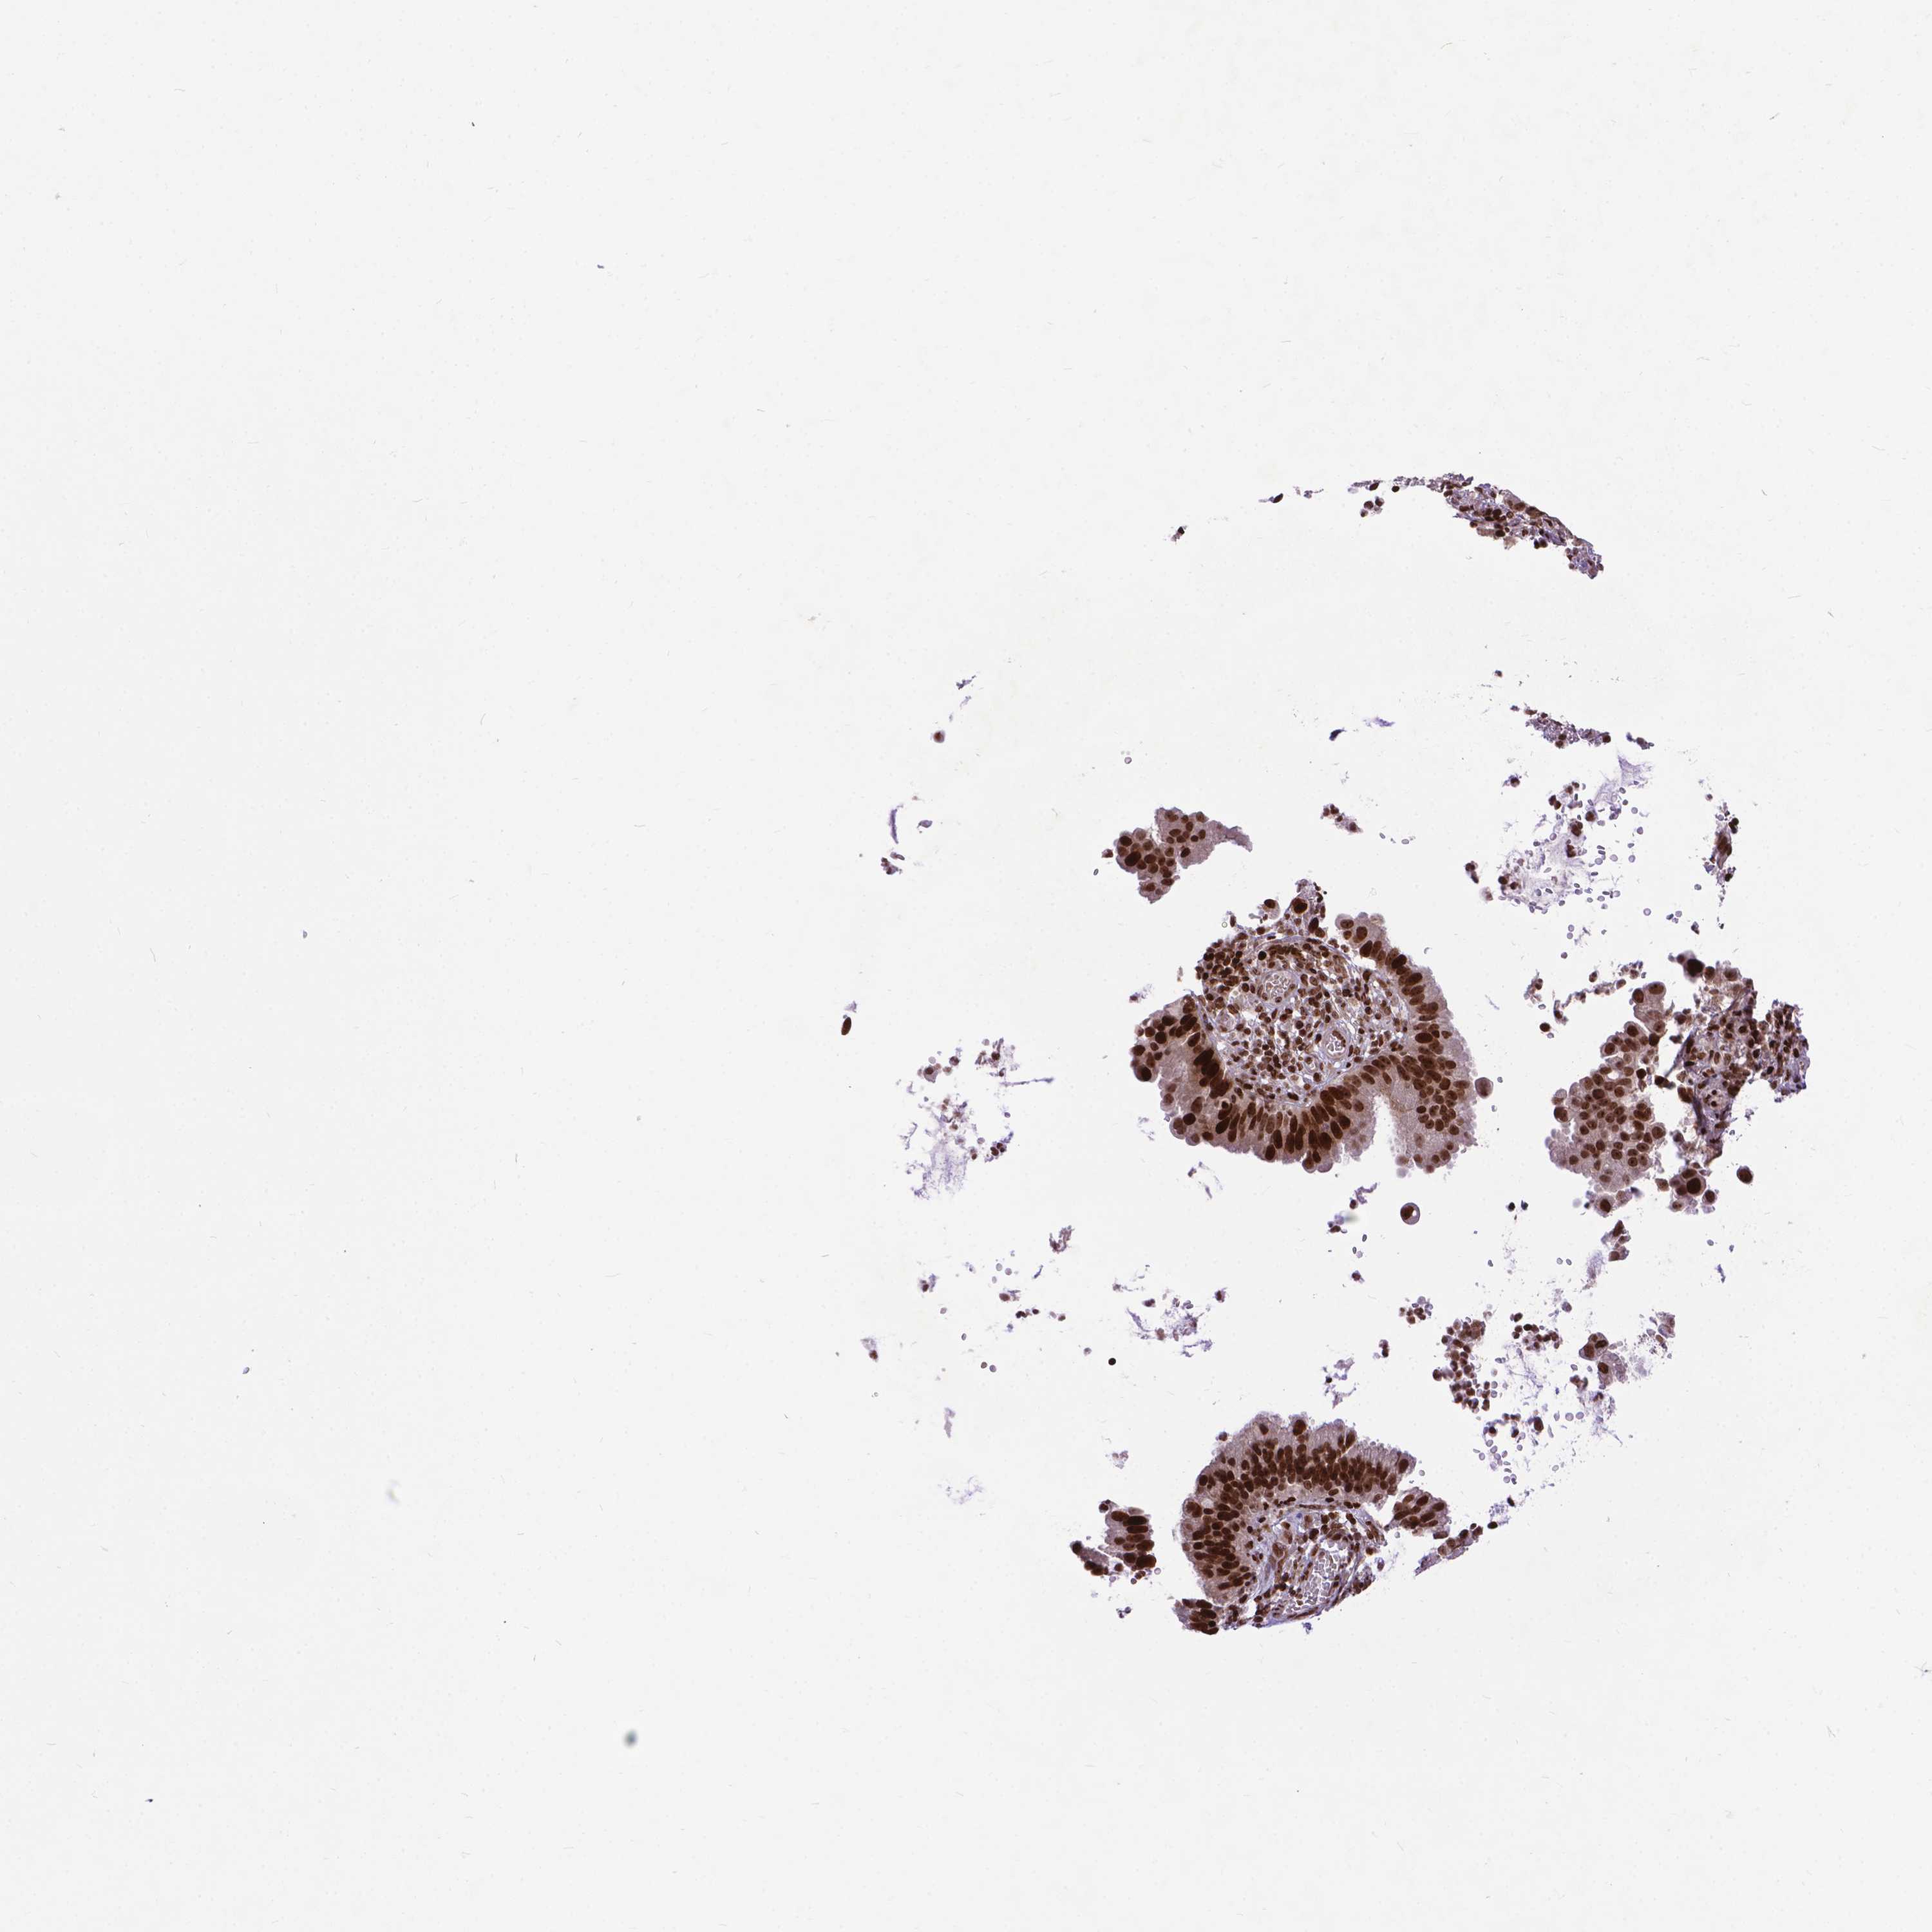

CERVICAL CANCER - Protein expressioni

A mouse-over function shows sample information and annotation data. Click on an image to view it in a full screen mode. Samples can be filtered based on level of antibody staining by selecting one or several of the following categories: high, medium, low and not detected. The assay and annotation is described here.

Note that samples used for immunohistochemistry by the Human Protein Atlas do not correspond to samples in the TCGA dataset.

Antibody stainingi

Antibody staining in the annotated cell types in the current human tissue is reported as not detected, low, medium, or high, based on conventional immunohistochemistry profiling in selected tissues. This score is based on the combination of the staining intensity and fraction of stained cells.

Each image is clickable and will lead to virtual microscopy that enables deeper exploration of all samples and also displays staining intensity scores, fraction scores and subcellular localization as well as patient and tissue information for each sample.

Antibody HPA065214

Staining

High

Medium

Low

Not detected

Intensity

Strong

Moderate

Weak

Negative

Quantity

>75%

75%-25%

<25%

None

Location

Nuclear

Cytoplasmic/membranous

Cytoplasmic/membranous,nuclear

Squamous cell carcinoma, NOS

Adenocarcinoma, NOS